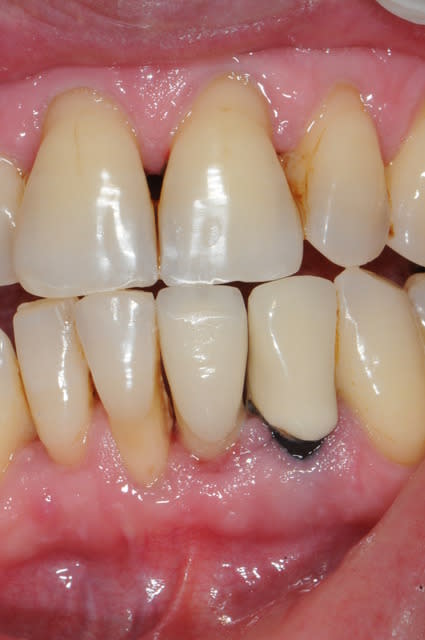

et ici ?? vous feriez quoi ?

32 et 42 pas mobiles

malheureusement, l'espace est réduit pour mettre deux implants.

comment avez vous déjà géré ce type de cas ??

le haut est déjà traité...

à propos du cas , j'ai vu avec la patiente cet aprem; nous avons décidé de faire un petit bridge provisoire de quelques mois et si (après traitement paro bien sure) les dents ne sont pas mobiles, on passera au bridge définitif. sinon, ce sera pose de deux implants en position 42-32 pour éviter une greffe que la patiente refuse.